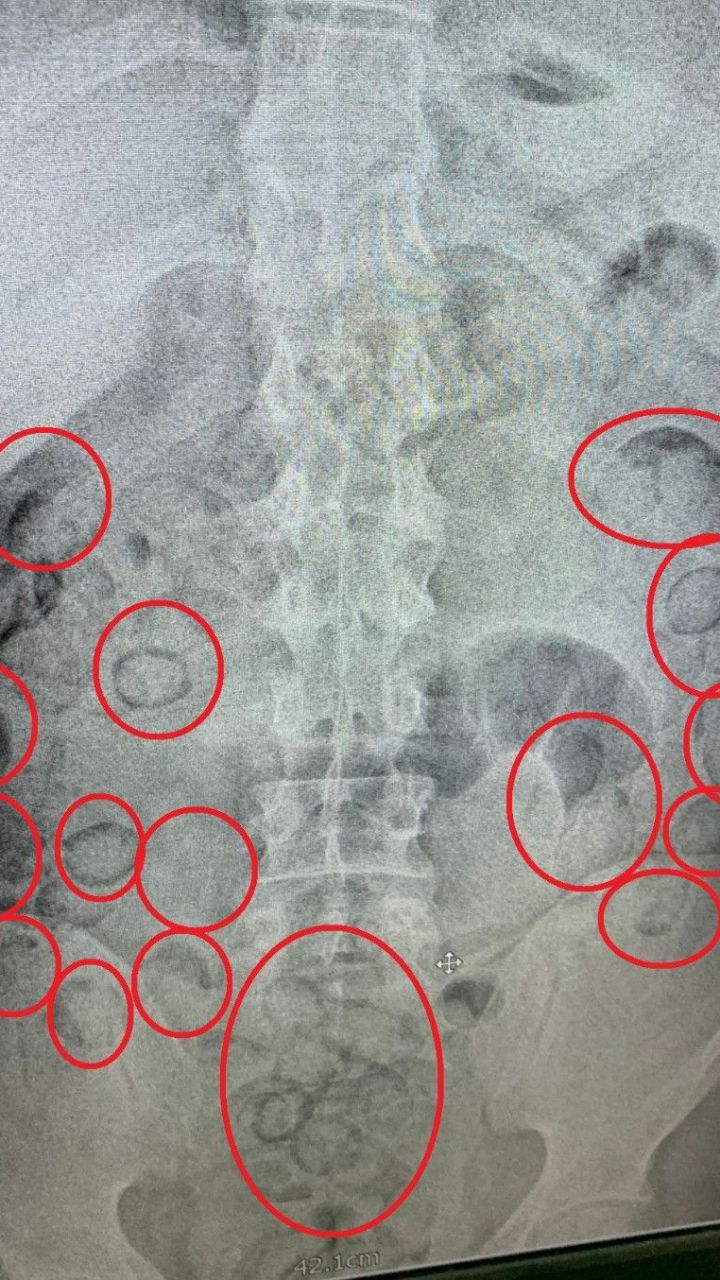

İranlı Uyuşturucu Taciri, Midesine Sakladığı 433 Gram Metamfetaminle Yakalandı

Narkotik Ekiplerinden Film Gibi Operasyon

Aksaray İl Emniyet Müdürlüğü Narkotik Suçlarla Mücadele Şubesi ekipleri, İran'dan Türkiye’ye uyuşturucu getirileceği bilgisini aldıktan sonra düğmeye bastı. Aksaray Cumhuriyet Başsavcılığı koordinesinde yürütülen operasyon kapsamında, İran uyruklu A.M. isimli şahıs teknik ve fiziki takibe alındı. Ankara’ya uçakla gelen şüpheli, otobüsle Aksaray’a hareket etti.

Uçaktan Otobüse, Oradan Gözaltına

Şüpheliyi adım adım takip eden ekipler, E-90 Karayolu üzerinde otobüsten indiği anda operasyon başlattı. Gözaltına alınan A.M.’nin midesinde uyuşturucu taşıdığından şüphelenen polis, şahsı Aksaray Eğitim ve Araştırma Hastanesi’ne götürdü. Burada çekilen tomografi sonucunda midesinde yabancı cisimler olduğu tespit edildi.

101 Paket Uyuşturucu Midesinden Çıktı

Doktor kontrolünde ilaç içirilen şahsın midesinden, büyük tuvaletini yaptığı sırada 101 adet prezervatife sarılmış paket çıktı. Paketlerin içinde toplamda 433 gram metamfetamin maddesi ele geçirildi. Emniyetteki işlemleri tamamlanan uyuşturucu taciri, çıkarıldığı mahkemece tutuklanarak cezaevine gönderildi.